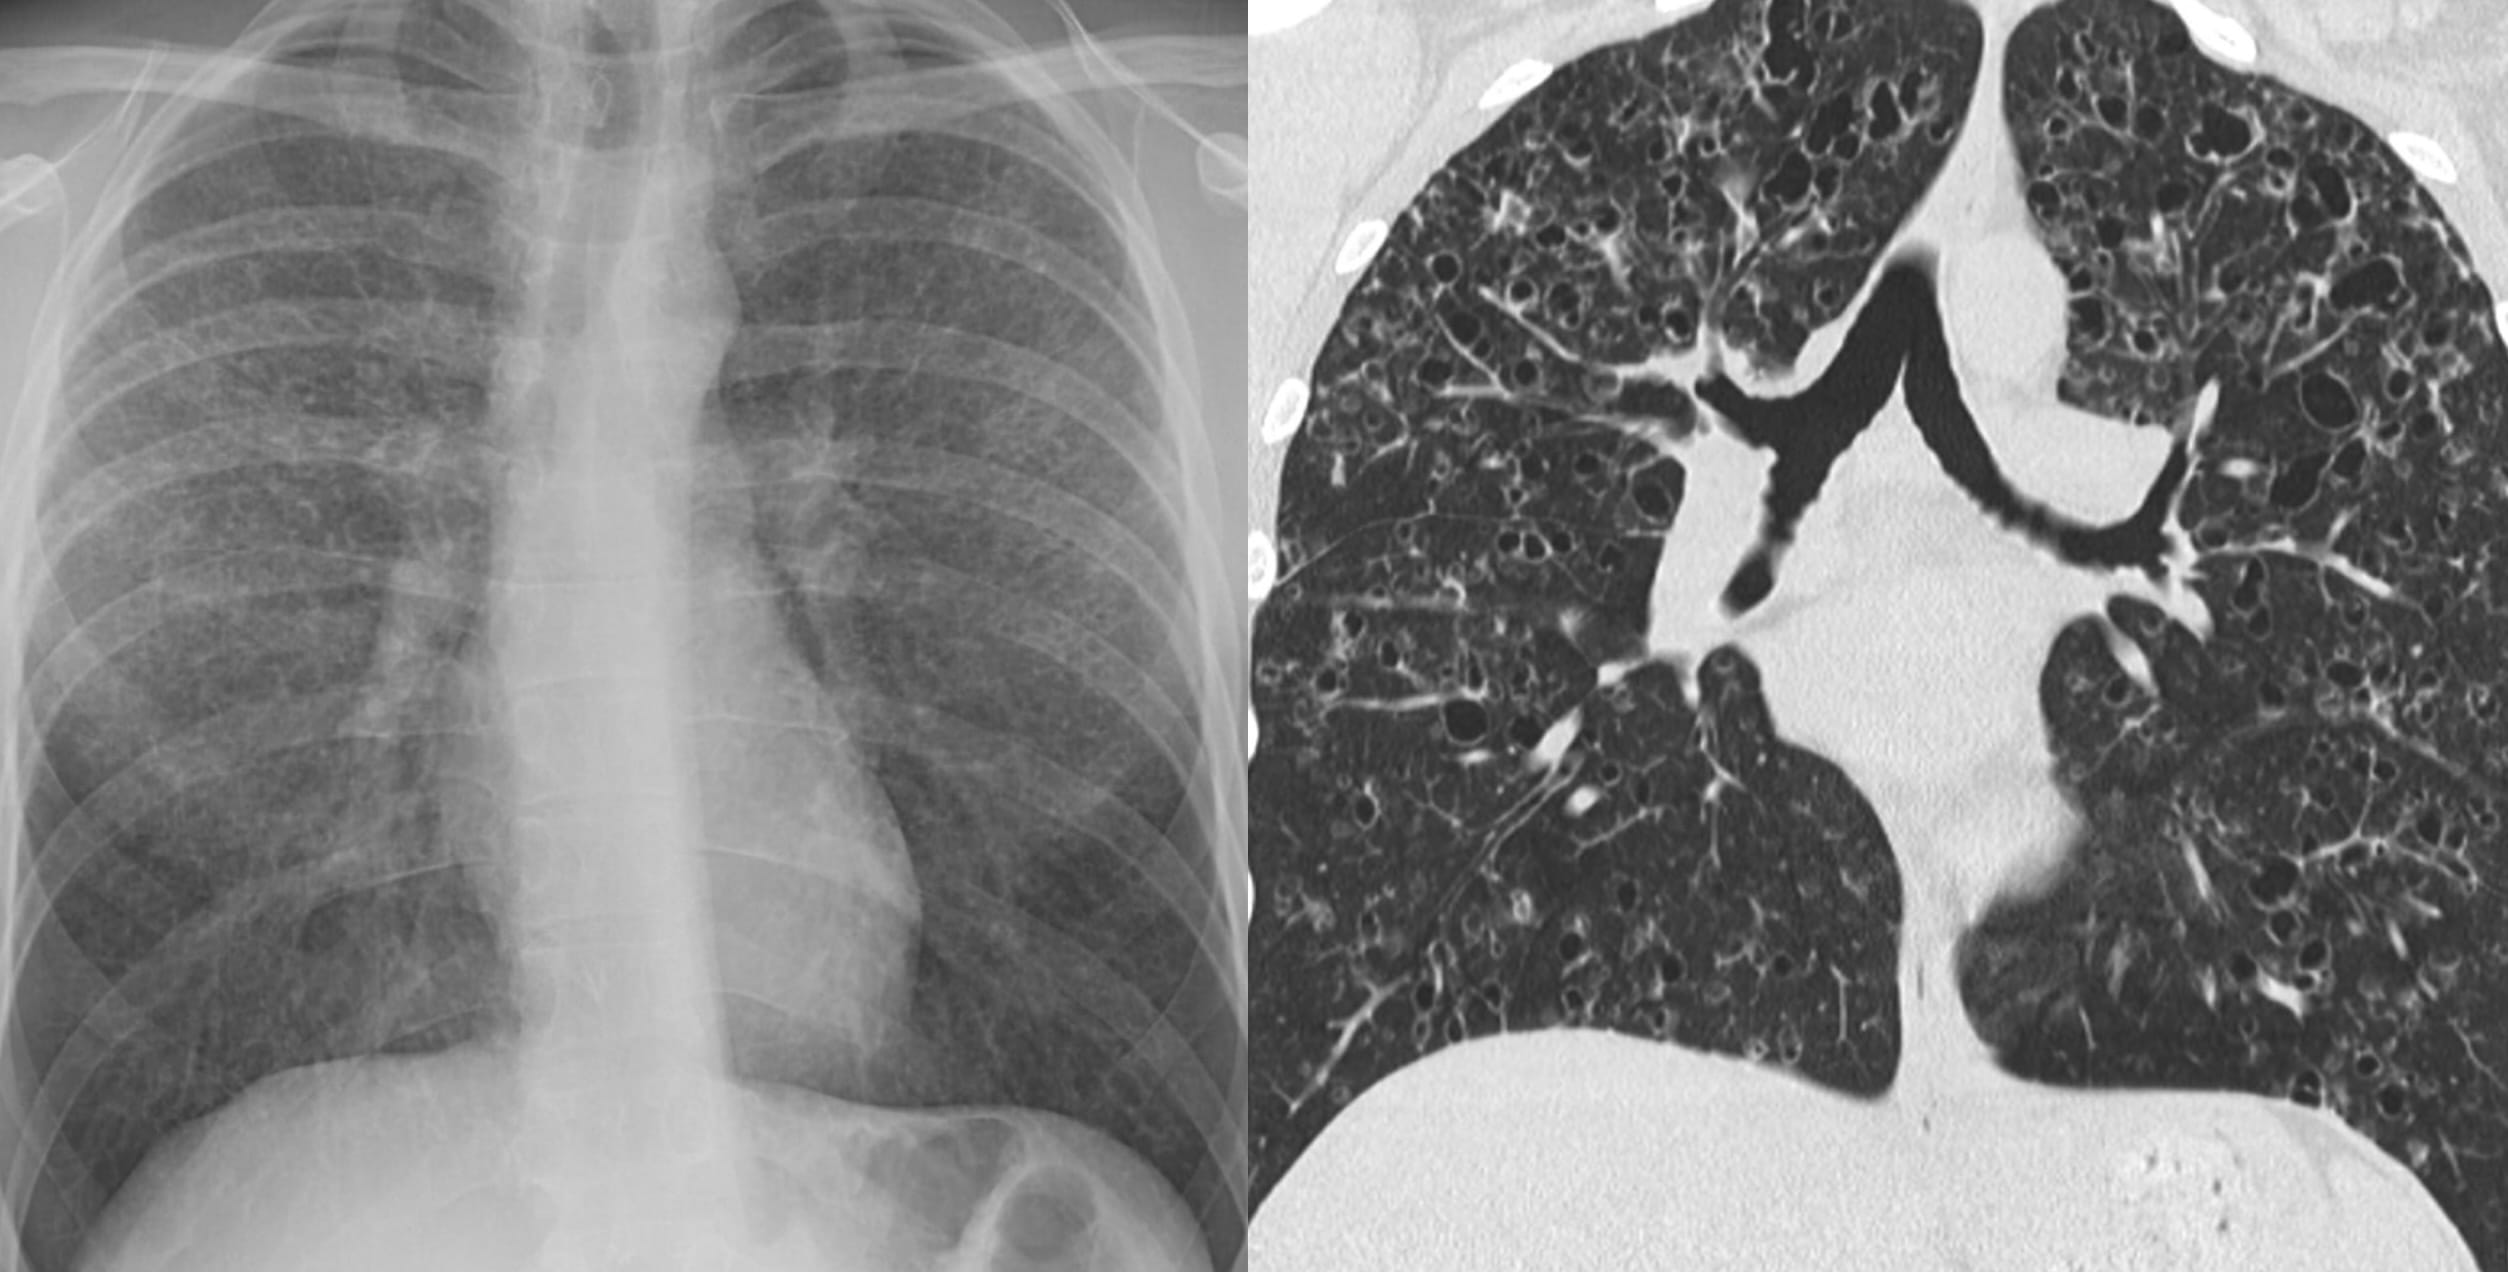

Airway-dominant phenotype

Emphysema-dominant phenotype

Mixed phenotype

We can make these distinctions on CT.

Note: bronchial wall thickening